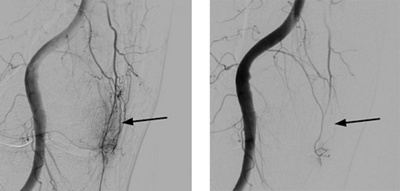

Mikro-Embolisation: Identifikation abnormer Gefässe auf der Innenseite des Kniegelenks (Pfeil linkes Bild), welche nach Einbringen des Medikaments (Embolisation) nicht mehr nachweisbar sind (Pfeil rechtes Bild).